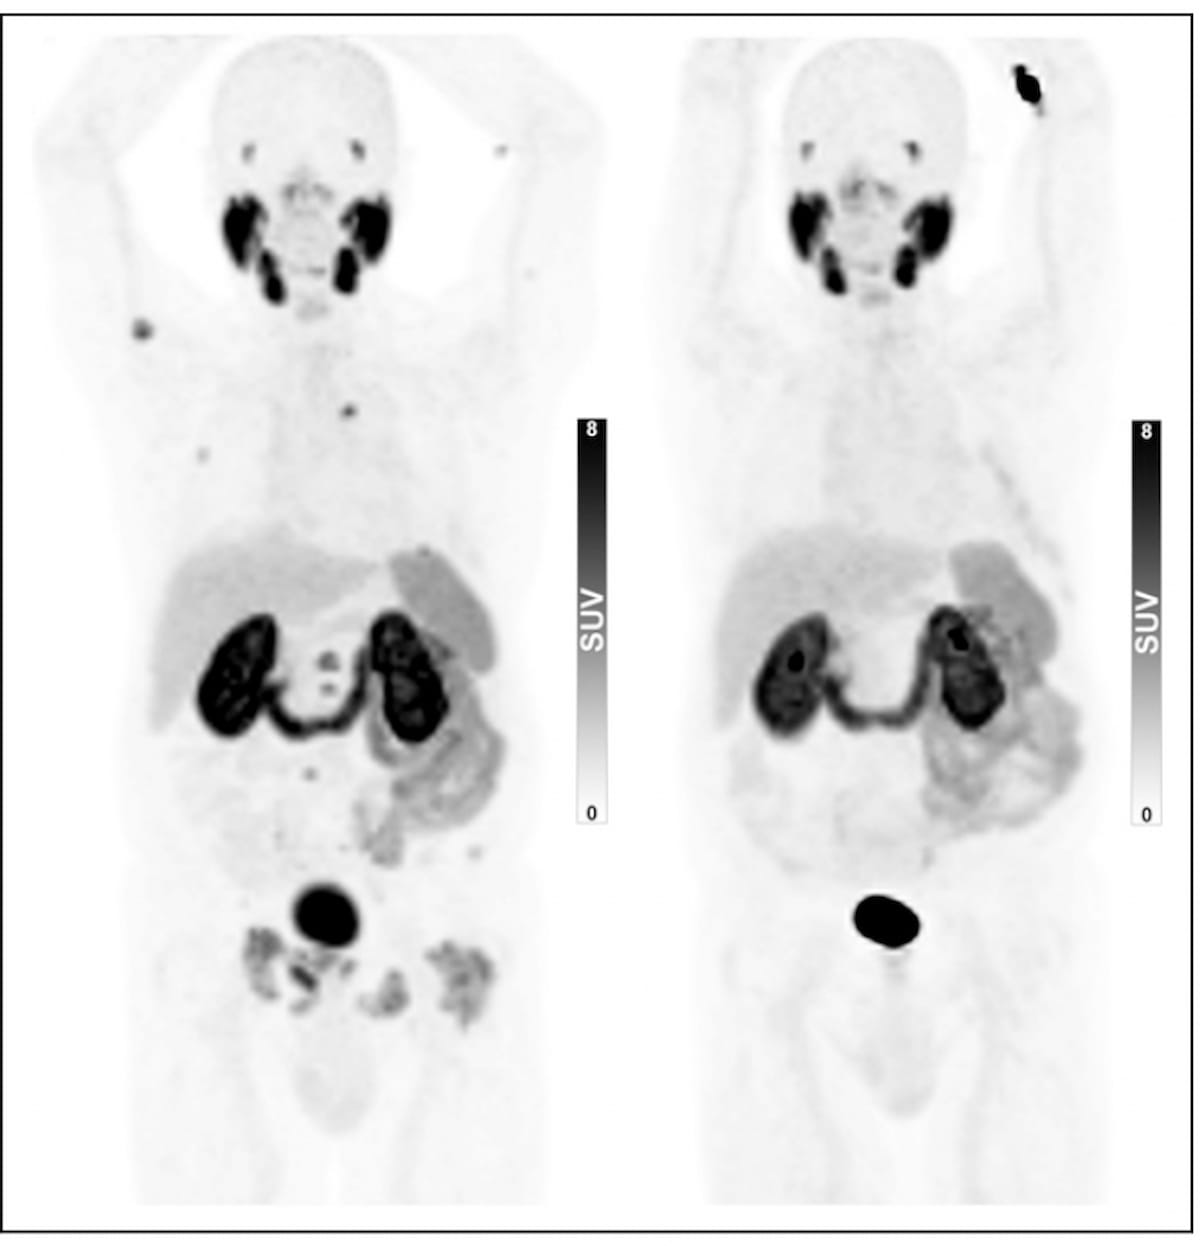

Examining the use of the Response Evaluation Criteria in Prostate-specific Membrane Antigen (PSMA) PET/CT (RECIP 1.0) model for assessing the treatment of metastatic castration-resistant prostate cancer, researchers found robust agreement between quantitative application of RECIP via tumor segmentation software and qualitative application of the model through reads by nuclear medicine physicians.